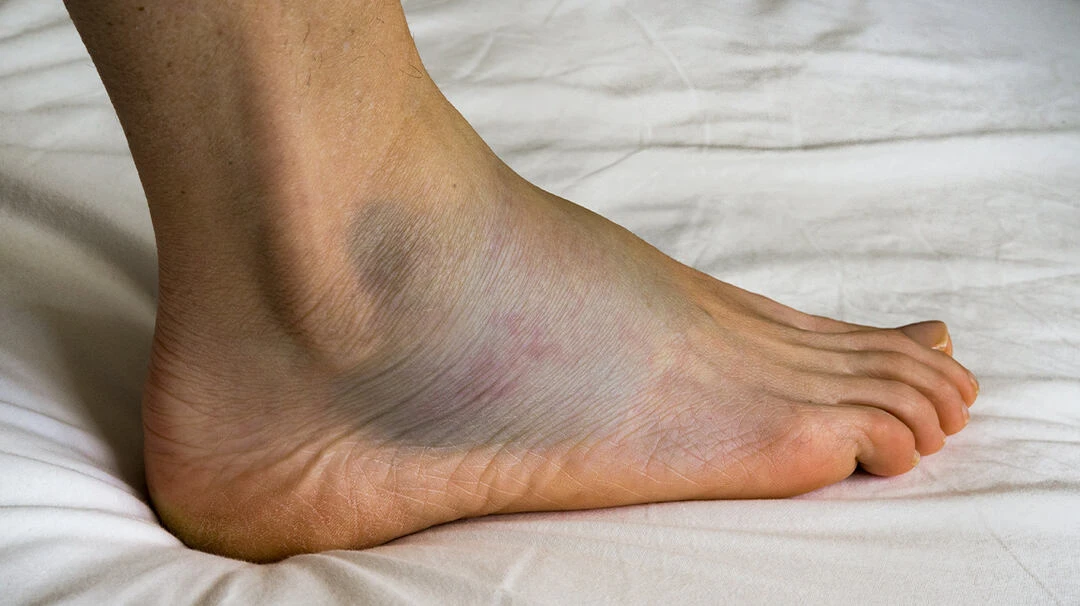

Dấu hiệu gãy chân lâm sàng

• Biến dạng chi:

- Sưng phù nề vùng gãy. - Có thể nhìn thấy rõ ổ gãy gồ dưới da. - Chân bị gãy nhìn ngắn hơn bên chân còn lại.